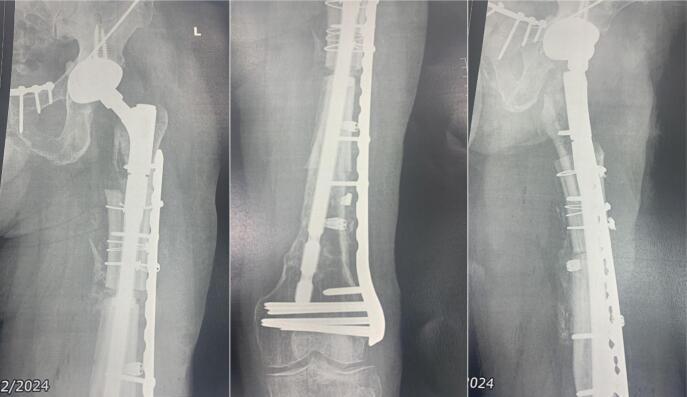

Defects in femoral bone segments represent a reconstructive challenge; they are caused secondary to multiple and extensive debridement in cases of patients with infections, tumors or high-energy trauma. Different treatments have been proposed to address this problem, however, these are limited when it comes to large defects that generate instability of the implants in the native bone as well as loss of functionality and length of the extremities. In the proximal femur, allograft prosthesis composites have been described in the management of extensive tumor resections, but they are not yet widely used in the management of bone defects due to osteomyelitis. The case of a 51-year-old male patient with post-traumatic pan-osteomyelitis of the femur Cierny-Mader IV with a 30-centimeter defect in whom limb salvage was achieved through the application of a femoral alloprosthesis is presented, exhibiting this surgical technique as an alternative in ample resections secondary to infectious processes in young patients, furthermore, offering a solution to the shortage of some prosthetic components in our surrounding.